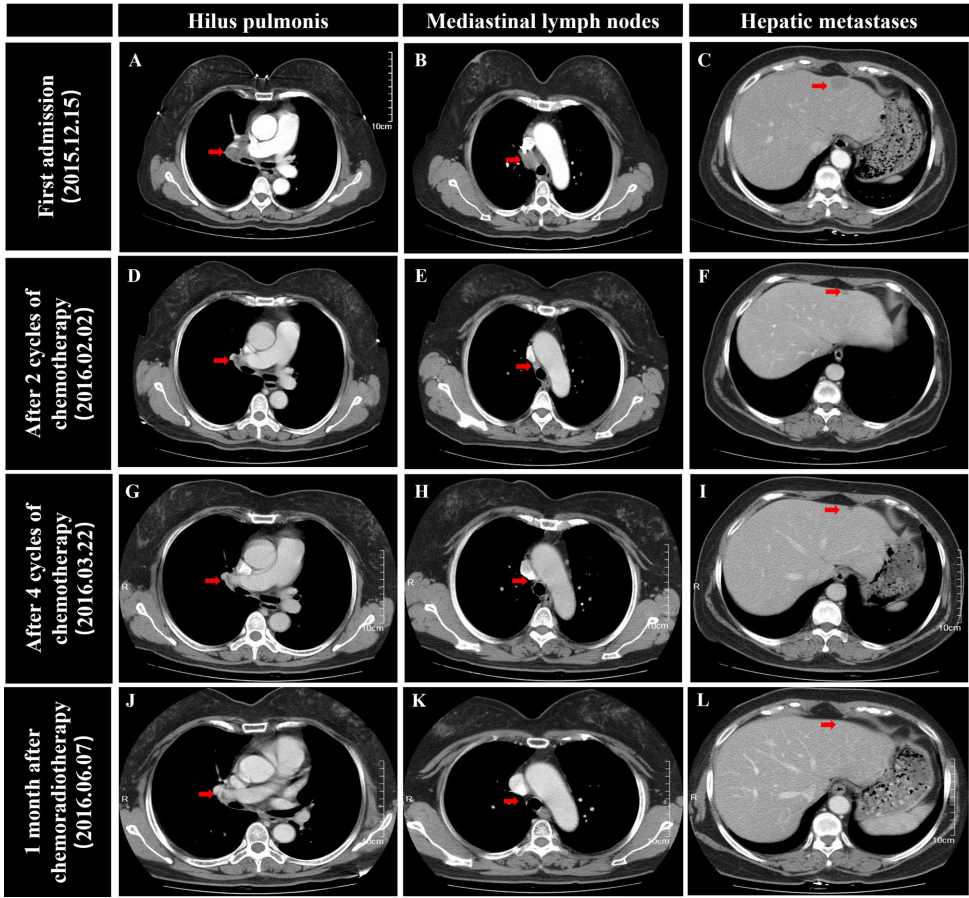

衢州市浙江医疗健康集团衢州医院(浙江衢化医院)肿瘤放化疗科的胡春秀、张明途等团队报道了一例突破常规生存期的典型案例。患者初诊为ES-SCLC伴肝转移,经6周期EP化疗+胸部放疗后获CR,48个月后复发采用EP+替雷利珠单抗治疗。研究通过动态监测肿瘤标志物(NSE)、影像学评估(CT/MRI)及免疫相关指标(淀粉酶/脂肪酶),结合病理活检排除胰腺肿瘤,证实了联合治疗的长期有效性及irAEs管理的重要性。